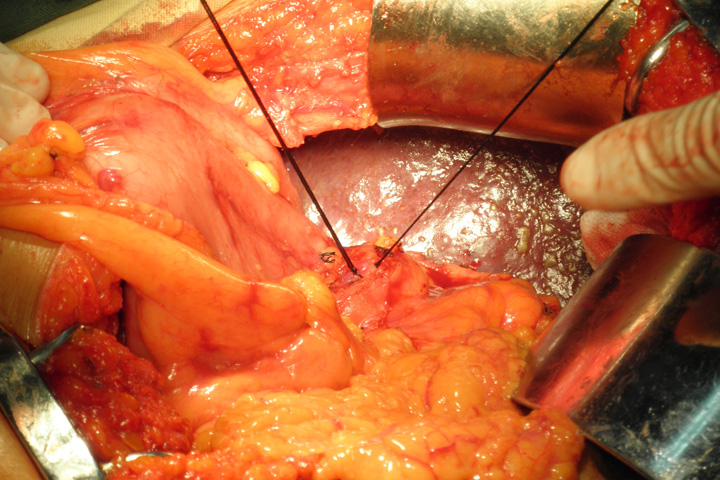

根据病、查体及上级医院相关辅助检查初步考虑灵床诊断为:肝硬化,门脉高压症,管胃底静脉曲张套扎术后,肝功能能失代偿期,低蛋白血症,低钾血症,脾功能亢进,肝功能B级。给予术前准备,于2012年10月29日行脾切除、门奇静脉断流术。术中诊断肝硬化,门脉高压,脾肿大、食道胃底静脉曲张。术后给予抑酸、抗炎、保肝、化痰支持及对症治疗。经系统治疗,患者生命体征平稳,一般状态尚可,切口愈合良好,已拆线,于2012年11月18日,术后第20日,病人及家属要求出院,向其交代病情,给予办理出院手续。- 上一个: 腹腔镜下胆囊切除术